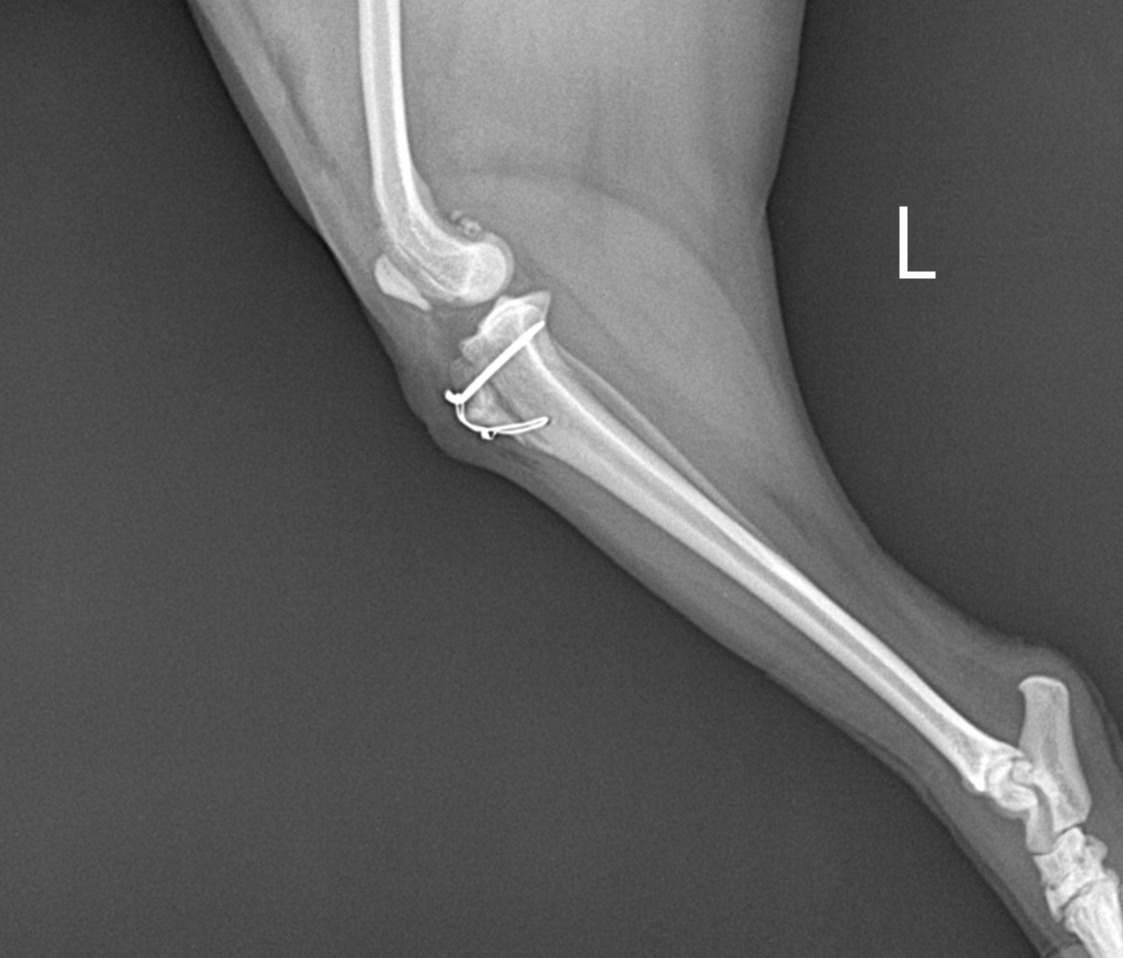

1603373244002-0.jpg 수술 후 핀으로 고정시킨 코코의 슬개골

우리를 보고 반갑다고 한달음에 달려오는데 마음이 짠했다. 의사 선생님은 코코 다리에 핀을 박았다고 했다. 잘 빠지지 않을 거라고 하시며 이후 상태는 집 근처에서 보기로 합의했다. 좋은 병원을 만나 수술을 잘 마치고 집 근처에 병원으로 다니며 주기적으로 엑스레이를 찍고 다리 상태를 살펴봤다.

- 엑스레이 사진 (병원에서 견주인 저에게 제공한 것으로 문제시 삭제하겠습니다.)